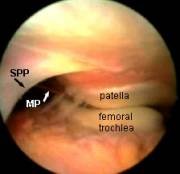

The medial plica sweeps along the side of the patella, but the suprapatella plica lies horizontally above the patella,and may stretch right across the joint cavity (the 'suprapatellar pouch').

Here the arthroscope has been withdrawn above the level of the medial plica to reveal the suprapatellar plica (black arrow). You can see its position in relation to the medial plica (white arrow), which is just draping itself out of sight over the front of the femur. REMEMBER, WE ARE LOOKING FROM ABOVE, WITH THE SCOPE IS THE LARGE CAVITY ABOVE THE PATELLA. You can't see this structure from the ordinary portals!